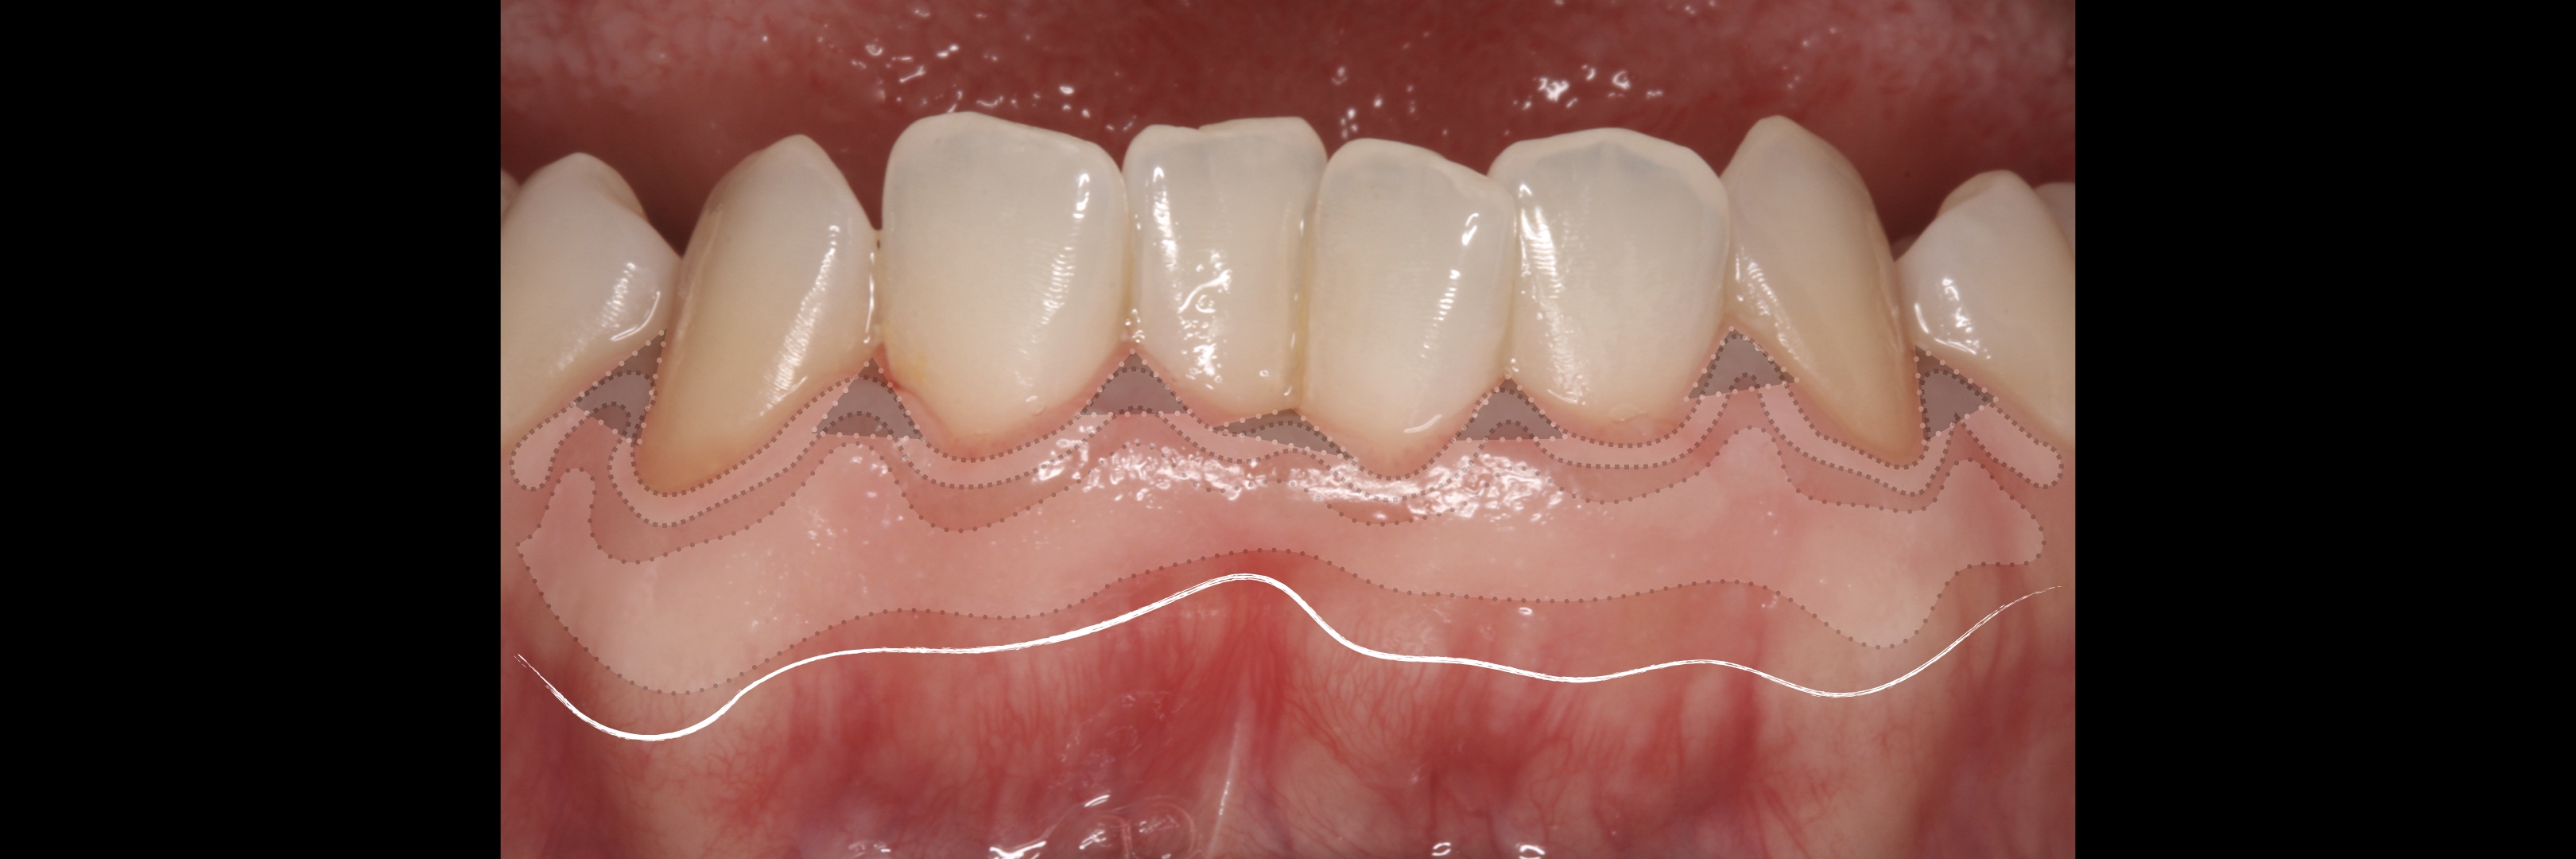

KERATINIZED gingiva includes

the free gingiva

(marginal gingiva & papillae)

and the attached gingiva extending from the gingival mar­gin to the mucogingival junction.

Generally we tend to forget about these 2 parameters, free and the attached gingiva are both essential parts of the keratinized gingiva.

This meaning that keratinized (load bearing capacity) is a mechanical characteristic that makes up for attached gingiva, providing it's immobility,  but also is of such importance as the thickness it provides around whatever perforates the epithelium, be it implants or teeth, being also keratinized (having load bearing capacity) at this location.

However free marginal gingiva is different in characteristics on its outer and inner surfaces: outer surface is keratinized;

inner surface is

non-keratinized, constituting part of the gingival sulcus.

The width of the keratinized gingiva may vary between 1 and 9mm.